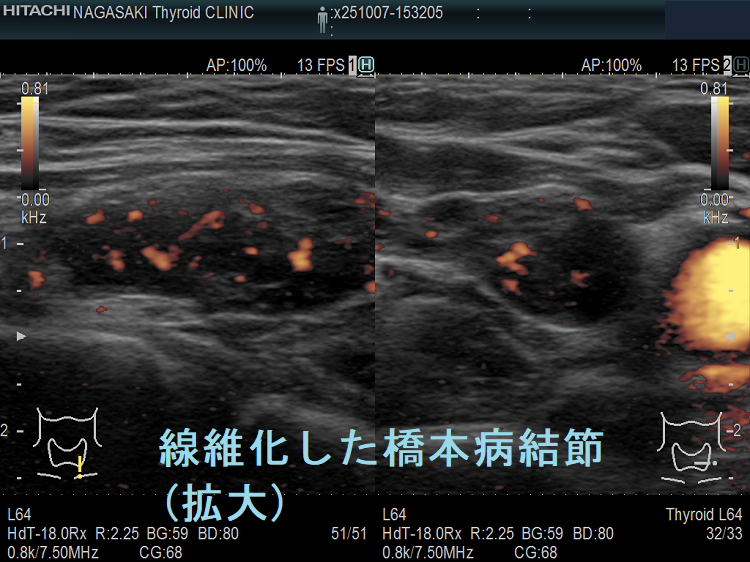

橋本病(慢性甲状腺炎)ではリンパ球浸潤に伴う炎症から濾胞細胞の好酸性変性[好酸性細胞(Hürthle細胞,ハーテル細胞)]・過形成、浮腫、線維化で結節性病変を形成[結節性橋本病(橋本病結節)]。病理学的に腺腫様甲状腺腫・腺腫様結節と同じで、橋本病(慢性甲状腺炎)を基盤とする腺腫様甲状腺腫・腺腫様結節。超音波(エコー)検査では内部が極めて低エコーのため甲状腺癌、甲状腺原発悪性リンパ腫と鑑別必要。細胞診では好酸性細胞、リンパ球集簇、炎症性多核巨細胞を認め、甲状腺乳頭癌ワルチン腫瘍型、通常型甲状腺乳頭癌・亜急性甲状腺炎と鑑別要。

橋本病(慢性甲状腺炎)では、リンパ球浸潤に伴う炎症から、濾胞細胞の好酸性変性・過形成、浮腫、線維化などの変化で結節性病変が形成されます[結節性橋本病(橋本病結節)]。病理学的には腺腫様甲状腺腫・腺腫様結節と同じ事で、橋本病(慢性甲状腺炎)を基盤とする腺腫様甲状腺腫・腺腫様結節になります。